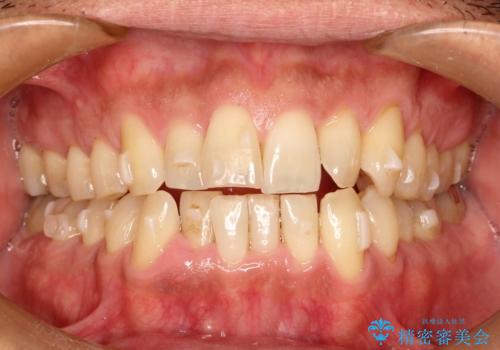

インビザライン invisalign ガタつきを治すマウスピース矯正

- 非抜歯・上顎臼歯遠心移動によるマウスピース矯正を計画した。

ガタつきを取り除くだけであれば非常に簡潔であるマウスピース矯正ですが、奥歯の位置関係の是正や、垂直的な歯の位置のコントロールなどが計画に含まれる場合、治療が難しくなってきます。